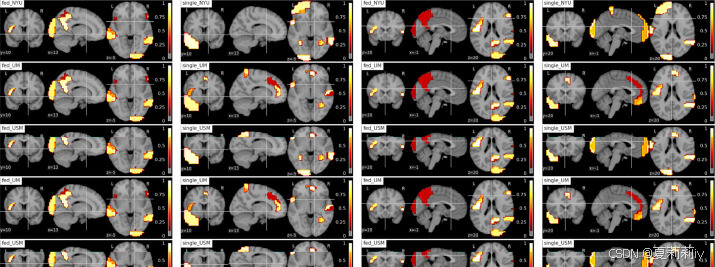

(3)Neural patterns: Connectivity in the autistic brain

①They define "informativity" as functional representation difference between ASD and HC groups and "robustness" as the biomarker consistency of 4 sites

②They applied guided back-propagation method to detect the robust biomarkers of HC in Fed:

③ASD biomarker:

④Function correlation: